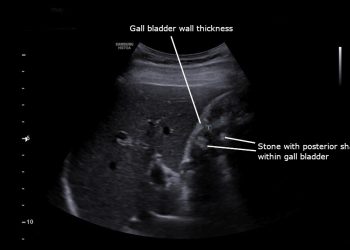

Acute CholecystitisDiagnosis and Treatment of Acute Cholecystitis 1 year agoDiagnosis and Treatment of Acute Cholecystitis. A quick...